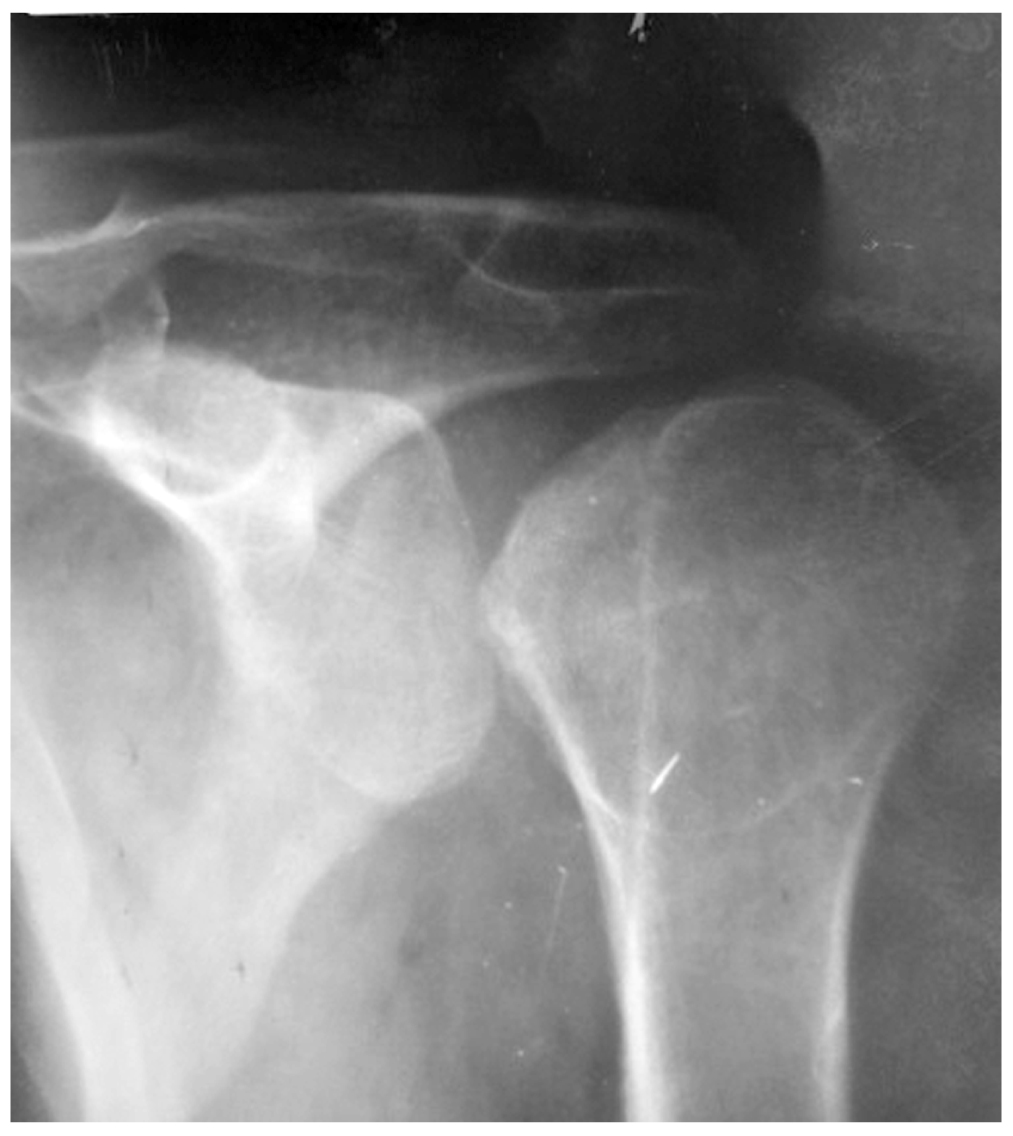

The postoperative period was showing no abnormalities; the limb was immobilized with the scarf bandage. The control radiology images show the correct positioning of the humeral head within the shoulder joint, with the humeral head projection zone showing the presence of two anchor fixation devices (Fig. 6). The immobilization with scarf bandage was used for 3 weeks with further restoring the mobility in the shoulder joint.

Fig. 6. X-Ray of the shoulder joint of patient (direct projection) after surgery.